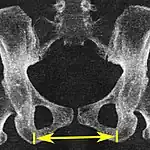

| Pelvic inlet | Transverse diameter of the pelvic inlet | ![]() |

![]() Coronal plane |

The iliopectineal lines, at widest transverse distance. | 13 to 14.5 cm.[4] |